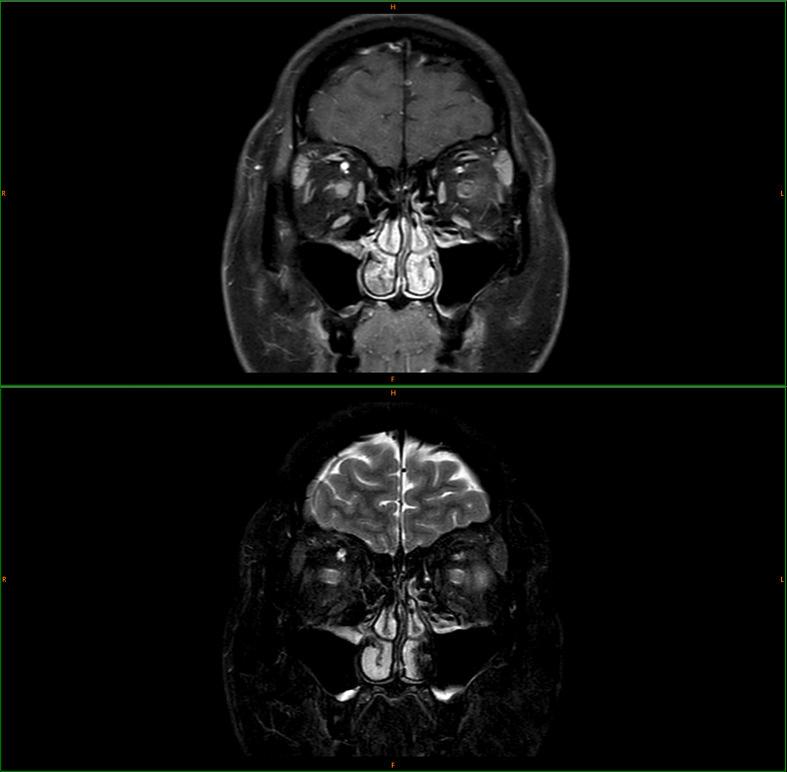

A 27-year-old woman complained of a throbbing headache for 2 weeks before developing visual loss in her right eye. She was diagnosed with presumed central retinal vein occlusion and was scheduled for further investigations. Two days later, she suddenly lost vision in her left eye and was admitted to the hospital. An eye examination revealed tortuous and dilated veins and optic disk swelling, notably in the right eye, compatible with venous stasis retinopathy in both eyes. Her right eye also had a premacular hemorrhage and vitreous hemorrhage. Magnetic resonance imaging showed an enhancement of bilateral optic nerves, and MOG antibody was detected in her serum. She successfully achieved a rapid improvement of vision in the left eye with intravenous methylprednisolone. However, her vision in the right eye did not recover due to dense vitreous hemorrhage.

一名27岁女性在右眼视力丧失前两周诉说搏动性头痛。她被诊断为疑似视网膜中央静脉阻塞,并计划进一步检查。两天后,她突然左眼失明并入院。眼部检查发现双眼静脉迂曲扩张以及视盘肿胀,尤其是右眼,符合双眼静脉淤滞性视网膜病变。她的右眼还出现黄斑前出血和玻璃体出血。磁共振成像显示双侧视神经强化,血清中检测到MOG抗体。静脉注射甲基强的松龙后,她左眼视力迅速改善。然而,由于严重的玻璃体出血,她右眼视力未恢复。